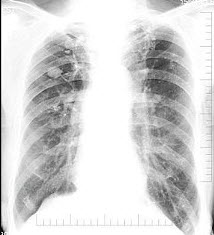

6、单项选择题

新生儿出生后出现气急、口吐白沫,呼吸微弱。床边X光片检查如图,最可能的诊断为()

A.新生儿肺炎